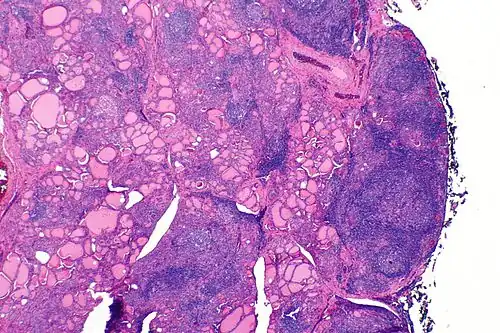

![]() | |

| A micrograph of the thyroid of someone with Hashimoto's thyroiditis | |

Gross morphological changes within the thyroid are seen in the general enlargement, which is far more locally nodular and irregular than more diffuse patterns (such as that of hyperthyroidism). While the capsule is intact and the gland itself is still distinct from surrounding tissue, microscopic examination can provide a more revealing indication of the level of damage.[55] Hypothyroidism is caused by replacement of follicular cells with parenchymatous tissue.[52]

Pathology

Gross pathology of a thyroid with autoimmune thyroiditis may show a symmetrically enlarged thyroid.[5] It is often paler in color, in comparison to normal thyroid tissue, which is reddish-brown.[5]

Microscopic examination (histology) will show lymphocytes (including plasma B-cells) diffusely infiltrating the parenchyma.[55] The lymphocytes are predominately T-lymphocytes with a representation of both CD4+ and CD8+ cells.[5] The plasma cells are polyclonal, with present germinal centers resembling the structure of a lymph node[5] (also called secondary lymphoid follicles, not to be confused with the normally present colloid-filled follicles that constitute the thyroid).[55]

In late stages of the disease, the thyroid may be atrophic.[10] Colloid-filled follicles shrink, and the cuboidal cells that usually line the follicles become Hürthle cells.[5] Fibrous tissue may be found throughout the affected thyroid as well.[5] Severe thyroid atrophy presents often with denser fibrotic bands of collagen that remain within the confines of the thyroid capsule.[55]

Generally, pathological findings of the thyroid are related to the amount of remaining thyroid function — the more infiltration and fibrosis, the less likely a patient will have normal thyroid function.[5] A rare but serious complication is thyroid lymphoma, generally the B-cell type, non-Hodgkin lymphoma.[24]